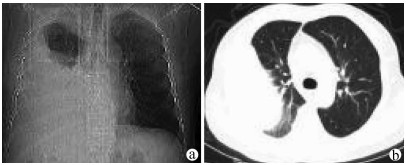

Treatment of refractory hepatic hydrothorax by intrapleural injection of lauromacrogol: A case report

Changzhou LI, Jianhui LI, Xin HAO, Haibin JIANG, Aimin WANG, Haiyang HUA, Jing QI, Jingzhe ZHANG

2021, 37(9): 2177-2179. DOI: 10.3969/j.issn.1001-5256.2021.09.033

Abstract(822) HTML (236) PDF (2488KB)(49)

Abstract: